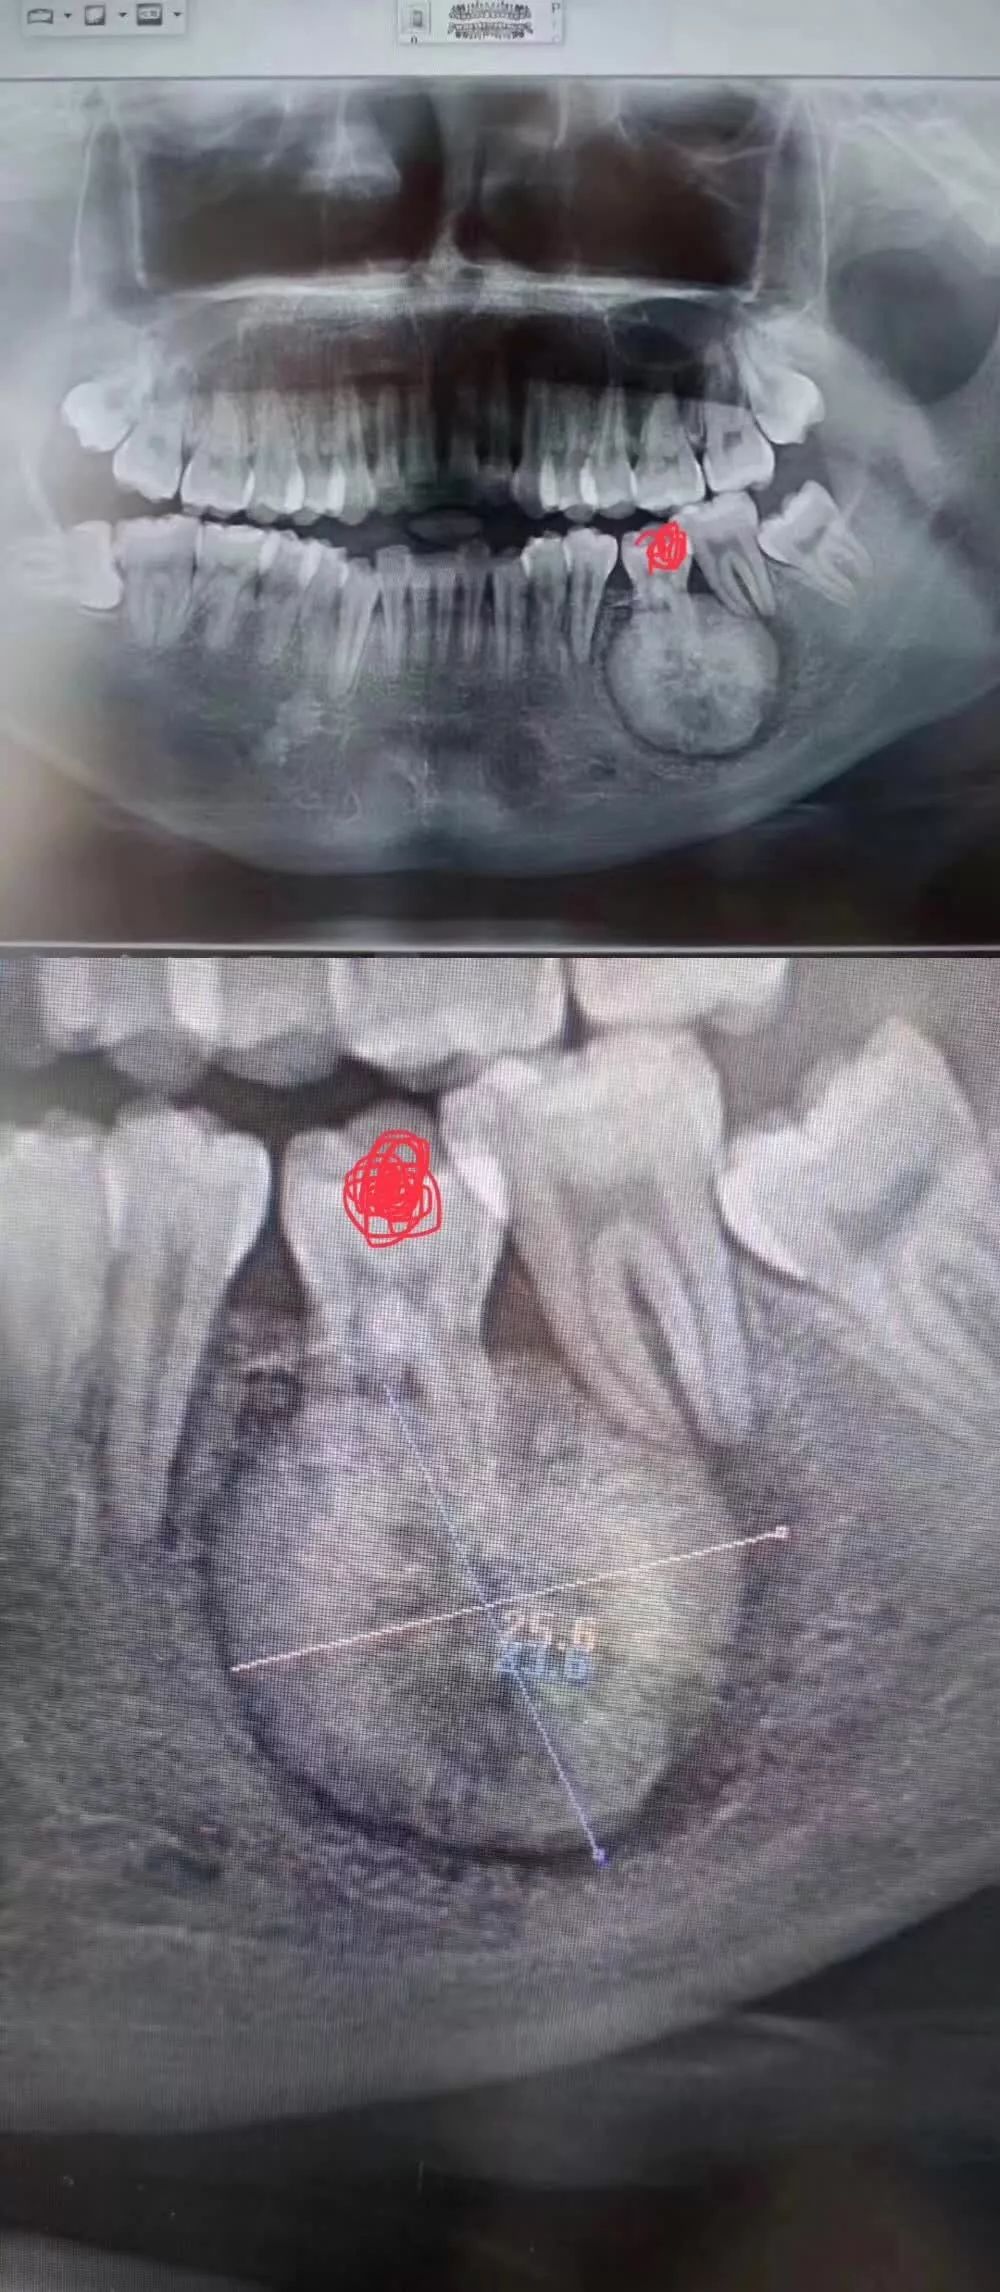

試想,如果冇拍片,直接貿然拔牙,一旦出現問題......一張牙片,“救”咗病人,更救了診所!

再嚟睇一個案例——

線片x線片唔止可以明白牙齒本身嘅病變情況,還可以明白牙根下有冇囊腫、周圍骨頭有冇吸收以及牙槽骨入面有冇埋伏牙、多生牙等。依據X線片綜合分析,可以提高齒科醫生診斷治療牙齒嘅準確性同成功率。

這裏要特別強調一下全景片,建議每個人一生要至少爲自己嘅牙齒拍一張全景片——

線片全景片不僅能瞭解牙齒本身嘅病變情況,還可以明白牙根下有冇囊腫、周圍骨頭有冇吸收以及牙槽骨入面有冇埋伏牙、多生牙等。